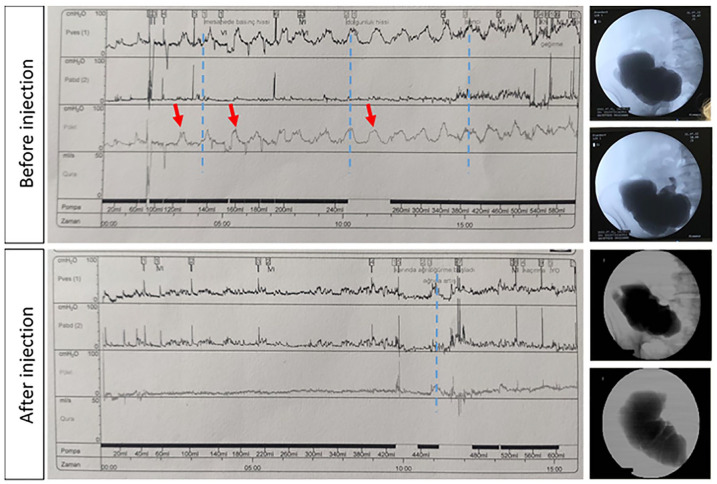

大陆尿转移是膀胱替代的首选方法,许多患者接受膀胱切除术良性条件。在大陆转移后,通常需要额外的干预措施以达到控制。其中一种手术是向新膀胱注射肉毒杆菌毒素。以前的囊膀胱注射都是经皮进行的。在这里,我们提出了一种微创内窥镜注射技术,在这种技术中,柔性设备已经成功地将肉毒杆菌毒素注射到囊袋膀胱中,通过囊袋口。我们证明了注射的可行性及其在减少眼袋收缩和患者症状方面的疗效。一位36岁女性在印第安纳州膀胱转移后1年出现持续性尿失禁症状。尽管先前的保守措施和回盲瓣强化手术,尿失禁仍然存在。内镜下注射,方便通过袋口,证明有效减少肌肉收缩和缓解痉挛样感觉,没有观察到的副作用。本病例证明了在内镜下印第安纳袋内注射肉毒毒素的可行性、安全性和有效性。

Continent urinary diversion is the preferred method of bladder substitution for many patients who undergo cystectomy for benign conditions. Additional interventions are often necessitated after a continent diversion to achieve continence. One such procedure is the injection of botulinum toxin into the neobladder. Previous injections into the pouch bladder have been performed percutaneously. Here we present a less invasive endoscopic injection technique where flexible equipment has been used successfully to inject botulinum toxin into the pouch bladder via the pouch stoma. We demonstrate the feasibility of the injection and its efficacy in reducing pouch contractions and the patient's symptoms. A 36-year-old female presented with persistent urinary incontinence symptoms 1 year after Indiana pouch diversion. Despite previous conservative measures and ileocecal valve reinforcement surgery, incontinence persisted. The endoscopic injection, facilitated through the pouch stoma, proved effective in decreasing muscle contractions and alleviating spasm-like sensations without observed side effects. This case shows the feasibility, safety and efficacy of botulinum toxin injection into Indiana pouch endoscopically.